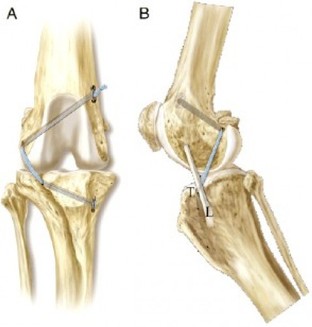

- Tightrope: è una tecnica recente, non richiede il taglio di osso come la TPLO o TTA. Sfrutta dei punti isometrici a livello di tibia e femore in cui vengono realizzati dei tunnel in cui all'interno passa un biomateriale sintetico per fornire la stabilizzazione.

- TTA è l'abbreviazione di tuberosità tibiale avanzamento.

E’ un intervento chirurgico intracapsulare per la terapia della rottura del legamento crociato craniale. La TTA fa parte delle tecniche chirurgiche che hanno come fine quello di ripristinare un equilibrio biomeccanico che neutralizzi la spinta craniale della tibia. L'obiettivo della chirurgia TTA è avanzare il sito di inserimento distale del tendine patellare cranialmente finché non è perpendicolare alla tangente comune che passa tra i condili femorali e quello tibiale. Gli impianti utilizzati per la TTA sono completamente in titanio. La chirurgia viene effettuata in Day-Hospital, nel post-operatorio è necessario osservare un periodo di convalescenza di circa un mese e mezzo.